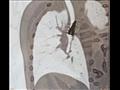

وقال الدكتور حسام العربي مدير مستشفى القلب في جامعة أسيوط، إنه جرى استقبال طفل يعاني من أعراض التهاب رئوي منذ شهر، وبعد توقيع الكشف الطبي عليه وإجراء الفحص والأشعة تبين وجود جسم معدني كبير في أسفل القصبة الهوائية وبداية الشعبة الهوائية اليمني، متابعًا "على الفور جرى إبلاغ فريق قسم جراحة القلب والصدر باتخاذ الإجراء الطبي اللازم".

وأشار الدكتور أحمد غنيم رئيس قسم جراحة القلب والصدر، إلى أنه فور تلقي القسم بيانًا بحالة الطفل المريض، جرت مناظرة الطفل بواسطة الأطباء عمرو ممدوح وأحمد سمير، والتأكد من وجود جسم معدني، وفقًا لما قاله والد الطفل إنه كان يلهو في الأرض ثم ظهرت عليه أعراض الكحة وضيق التنفس.

وأكد "غنيم" إجراء المنظار على الشعب الهوائية للطفل، واستخراج جسم معدني كبير من أسفل القصبة الهوائية؛ مشيرًا إلى خروج الطفل بصحة جيدة بعد التأكد من استقرار حالته الصحية.